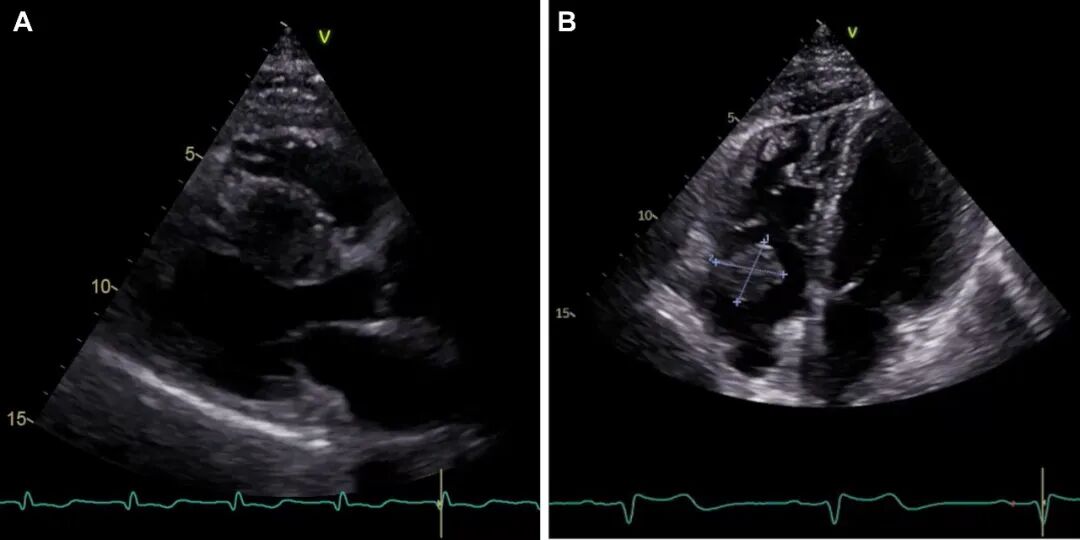

图1. A超声心动图长轴切面显示一个部分坏死的圆形肿块,位于室间隔中段基底部,导致室间隔假性肥厚。B带蒂肿块,起源于右心耳,累及房室口。

全身CT扫描显示,与2023年CT扫描相比,双侧多发性肺部肿块大小进一步增加(左侧最大者7.2 cm对比6.2 cm),边缘清晰,内部可见粗糙的血管结构和坏死液化灶(图2)。未检测到额外结节。在奇异食管凹陷处报告的部分实心结节为实心圆润,测量为11毫米(对比9毫米)。证据显示右上肺叶和同侧下肺叶需进行楔形切除。检查未发现其他器官有其他病变。心脏磁共振显示室间隔中段基底部有一大肿块(最大尺寸,5×35cm)(图3A)。对比剂注射后序列显示不规则晚期钆增强,提示右心房存在一个通过细长蒂附着的肿块(最大尺寸,2.5×3cm)(图3B),该肿块在对比剂注射后序列中未见晚期钆增强。